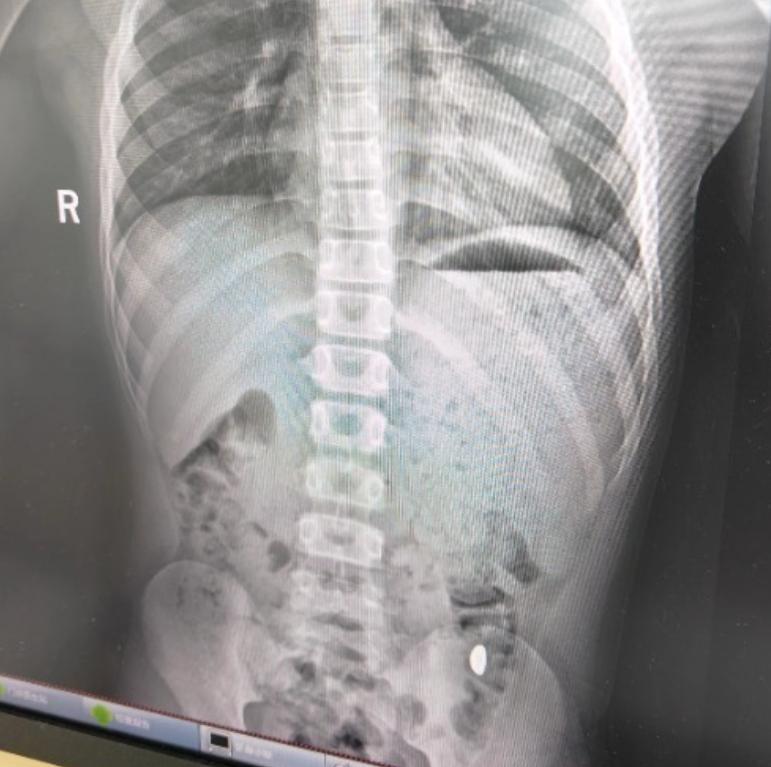

“不作就不会死!”10月27日,江苏昆山,一11岁男孩将妈妈的10克金豆子含在嘴里玩,谁知他一个不小心竟然把金豆吞了下去,妈妈天天嘱咐男孩不要在外面上厕所,网友:在外面如厕的代价有点太大了! 半大男孩正是调皮的时候,他们往往想到什么有趣的事情就会立刻做,根本不考虑后果,一些危险物品照样往嘴里放。 一男孩拿着妈妈万元购入的10克金豆子把玩,他突发奇想,打算用这颗金豆子锻炼自己舌头的力量,于是男孩将金豆含在嘴里转圈。 不料,由于男孩舌头转动速度太快,不慎将金豆顶到了嗓子眼,随后他直接将金豆子吞了下去,这可把男孩吓了一跳,他想到电视剧里一些“吞进自杀”的情节,哭着跑去告诉妈妈自己吃了金豆子,可能要“死”了。 妈妈一开始还以为男孩在开玩笑,没想到竟然是真的,她十分无奈,打算让男孩自行排出,害怕金豆遗落在外,还天天嘱咐孩子不能在外面如厕。 五天之后,男孩还是没有排出金豆,妈妈带他来到了医院,好在当天下午金豆子被顺利排出,男孩的身体也无大碍。 不少网友表示,男孩这要是在外面如厕时排出金豆子,这个代价未免也有点太大了,贵重物品一定要妥善保管,也要提醒孩子不要做出危险的行为! 信息来源:《11岁男孩误吞10克金豆,妈妈:天天叮嘱他不要在外面大便》大象新闻